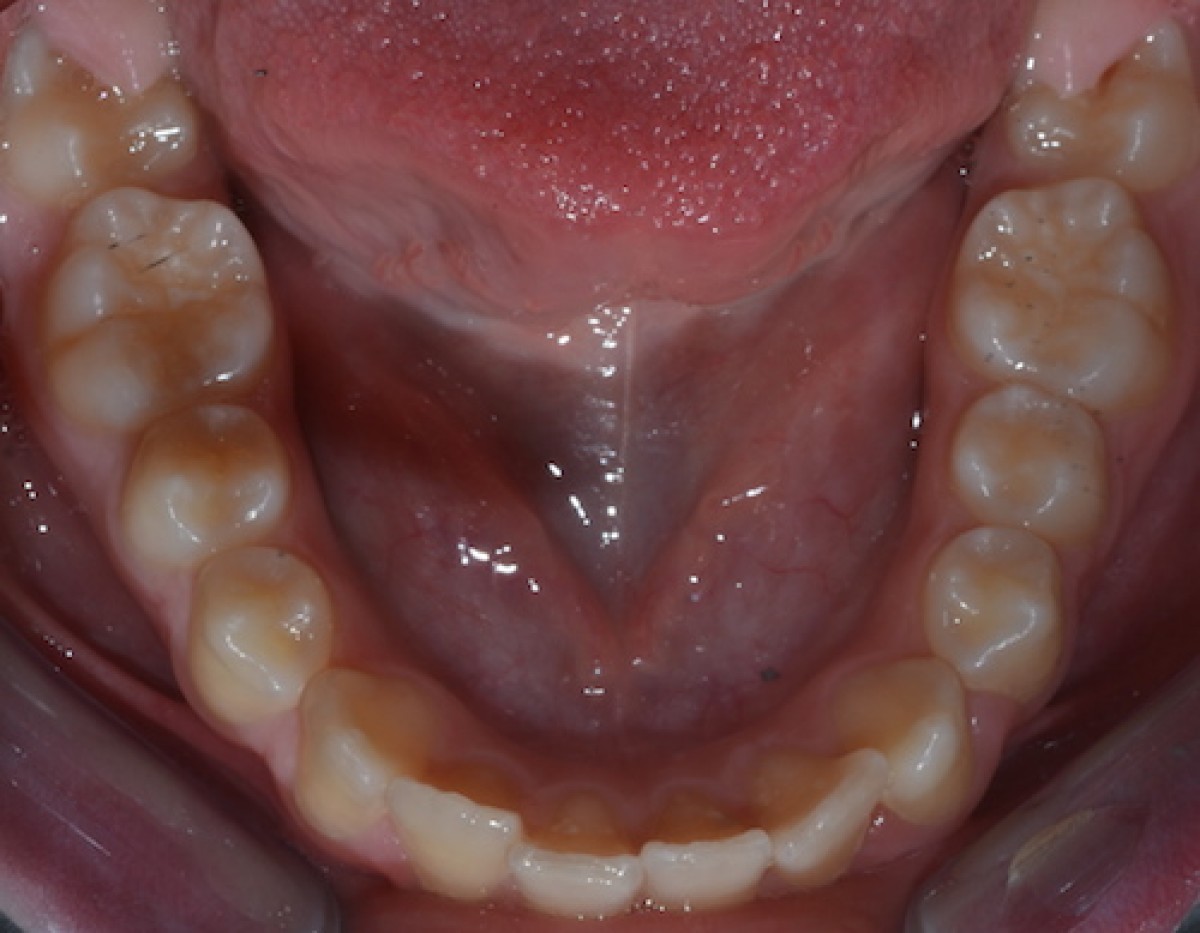

A healthy Caucasian girl presented with a skeletal class I, molar class I, dental overcrowding and exhibiting overbite increased prior to treatment. According to the IOTN index, the patient displayed a grade 3 treatment requirement. The patient showed a medium grade of dental crowding in both dental arches. For treatment, the authors only used the EQ O.S.A. device (equilibrator designed by Ovidi, Santi, Aprile for Eptamed SRL; Cesena, www.eptamed.com).

the authors successfully treated an orthopaedic/orthodontic case with a simple device that is described herein. After two years of using this device, the IOTN index passed from grade 3 to a grade 1.